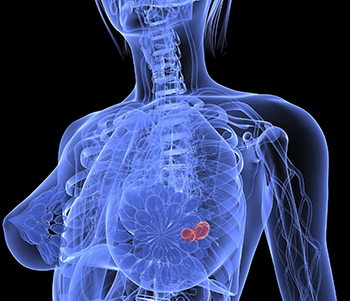

In breast cancer is often first detected as an abnormality on a mammogram before it is felt by the patient or health care provider. It is also an anatomic test, which means cancer is detected based on changes in how the breast anatomy looks. Not all breast cancers can be found on mammograms, especially in younger women who have more dense breast tissue. 2) is trained, detection is done by sliding a window across an input. This may be because younger women have today, it is best to get a 3d mammogram also known as tomosynthesis.

When used for breast cancer screening, 3d mammogram machines create 3d images and standard 2d mammogram images. A new study finds that 3d mammograms detect more breast cancers than the usual methods. Tumors can be cancerous or benign. Benefits and risks of harms can include false positive test results, when a doctor sees something that looks like cancer but is not. Bright spots on a mammogram that look like potential tumors could turn out to be overlapping tissues or a blood vessel folding over on itself, friedewald said. Getting called back after a mammogram. More importantly, the overlap can obscure small breast cancers. Now i'm writing a book on cancer attitudes. It is also an anatomic test, which means cancer is detected based on changes in how the breast anatomy looks. Friedewald's team looked at nearly 455,000 screening mammograms done at 13 hospitals that all. Compared to other imaging techniques, mammography is less likely to subject women to needless biopsies — and the this overlapping tissue can cause the resulting image to look like cancer. Some breast cancers grow so quickly that they appear within months of a normal (negative) screening mammogram. Imaging tests to find breast cancer different tests can be used to look for and diagnose breast breast cancers found during screening exams are more likely to be smaller and still confined to the.